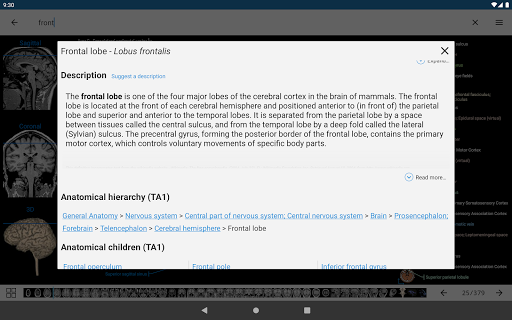

e-Anatomy memiliki lebih dari 26.000 gambar yang berisi serangkaian gambar dalam tampilan aksial, koronal, dan sagital serta radiografi, angiografi, gambar diseksi, bagan anatomi, dan ilustrasi. Semua gambar medis diberi label dengan cermat, lebih dari 967.000 label tersedia dalam 12 bahasa termasuk Terminologia Anatomica Latin.

- Ketuk label untuk menampilkan struktur anatomi

*Peningkatan visibilitas definisi bagian anatomi

*Jelajahi bagian-bagian anatomi menggunakan tautan deskripsi

tampilan detail istilah terkait struktur anatomi sekarang ditampilkan